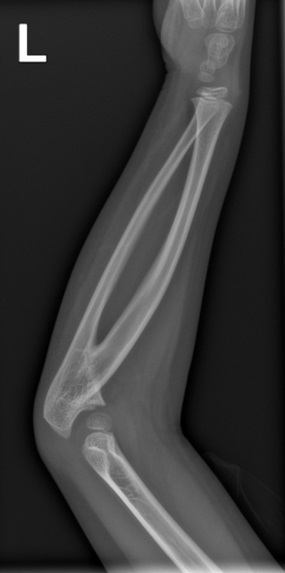

Pruebas complementarias: radiografía simple lateral de ambos codos, sinostosis radiocubital proximal, con ausencia de cabeza de radio e incurvación proximal del mismo (Figura 1).

Figura 1. Radiografía del brazo